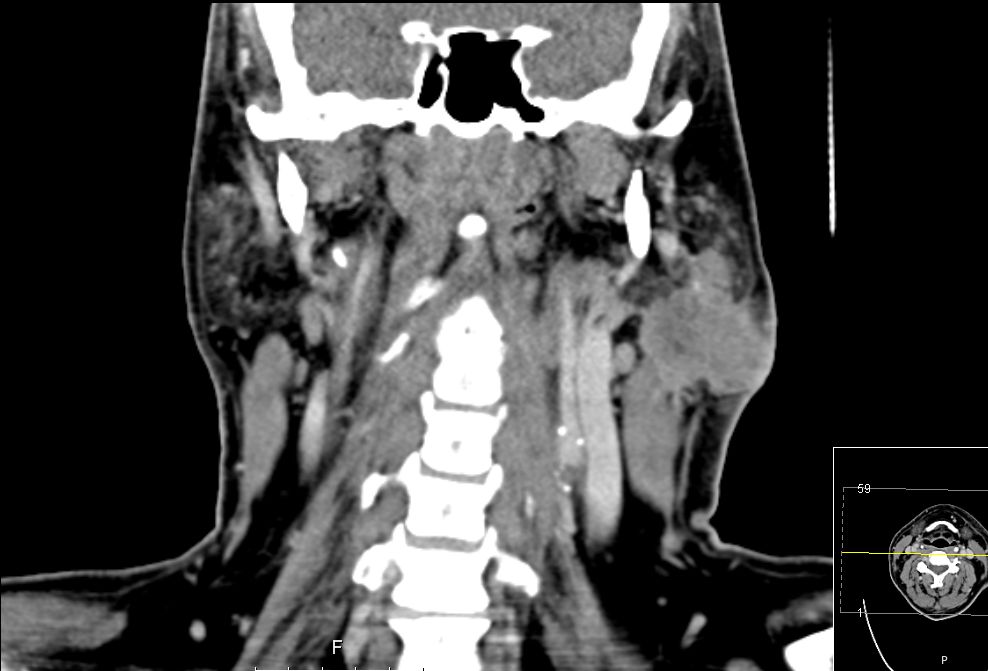

| CT | 51-jähriger Mann, der eine Gesichtsschwellung bemerkte. Adenokarzinom pT3 pN1 Mo L1 G3. Subtotale Protidektomie unter Neuromonitoring, ND LI und II links, Adjuvante RT. ![]() |